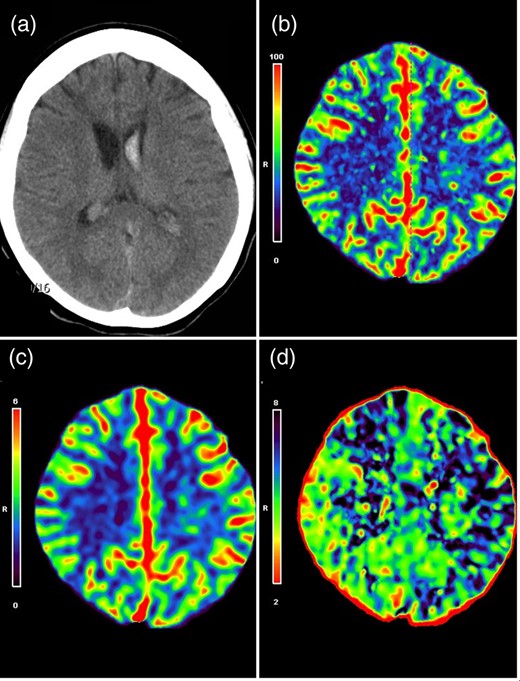

Cerebral digital subtracted angiography (DSA) revealed typical angiographic findings of moyamoya disease, which included bilateral stenosis in the terminal portion of the internal carotid arteries (ICAs) and formation of abnormal vascular networks in the region of the choroidal arteries and basal ganglia (Fig. 2a). The AChA on the left side was significantly enlarged, and provided collateral supply toward the periventricular brain parenchyma. Multiple angiographic weak points, characterized by irregular segmental dilatations and pseudoaneurysmal formation, were also noted along the intraventricular segment of the AChA (Fig. 2b).

Anteroposterior (a) and lateral (b) views of the right ICA angiogram demonstrated severe stenosis of the ICA termination, formation of moyamoya collateral network and multiple weak spots (dashed arrows: irregular segmental dilatations; single arrow: pseudoaneurysm) along the enlarged intraventricular segment of AChA. (c) Right external carotid angiogram demonstrated a robust collateral formation (asterisk) underlying the site of pial synangiosis. (d) Right ICA angiogram demonstrated that previous weak spots observed along the intraventricular AChA segment (double arrows) significantly regressed or disappeared.

As all these observed weak spots might be the source of the hemorrhage, the precise bleeding point could not be identified. In addition, trapping of the whole intraventricular AChA segment also carried a risk of interruption of this important collateral supply. Therefore, our treatment strategy was to perform an indirect surgical revascularization on the left hemisphere first in order to decrease collateral needs from the AChA. An additional neuroendovascular occlusion of the distal AChA could be considered later if the weak points failed to regress.

An encephalo-duro-arterio-synangiosis procedure was performed on the left hemisphere. DSA 1 year after surgery demonstrated robust collateral formation underlying the site of pial synangiosis (Fig. 2c). All weak points observed along the AChA had markedly decreased in caliber or disappeared (Fig. 2d). Therefore, additional treatment was not necessary, and the patient remained symptom-free for 4 years.